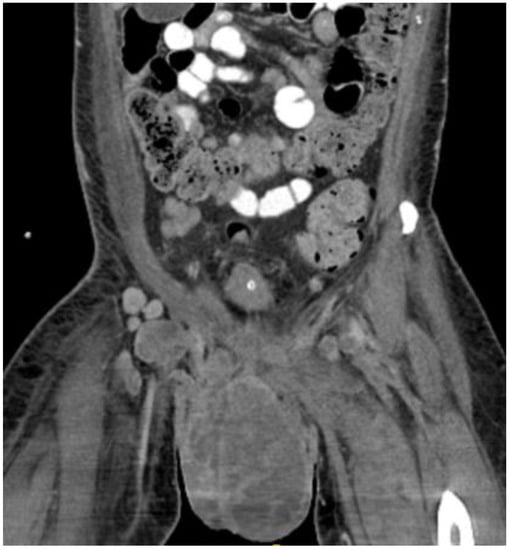

Figure 6.

CT scan in the axial view, abdominal window, showing scrotal mass extending through the anus with involvement of ischial tuberosity.